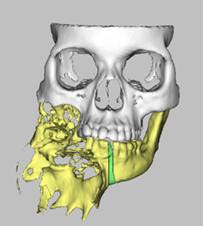

Figura 2: A - Computed tomography 3D reconstruction image of a patient with extensive Ameloblastoma; B- Virtual surgical planning

Ameloblastoma Treatment (Fig6): Two mandibular resections and reconstructions with titanium plates were performed to remove extensive tumors while preserving jaw functionality.

Figure 6: Computed tomography image of a patient with extensive ameloblastoma